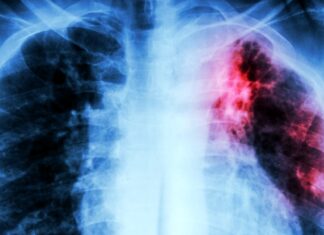

Tuberkulose (TB), eine Krankheit, von der früher angenommen wurde, dass sie auf dem Rückzug ist, ist weltweit wieder auf dem Vormarsch und zunehmend resistent...